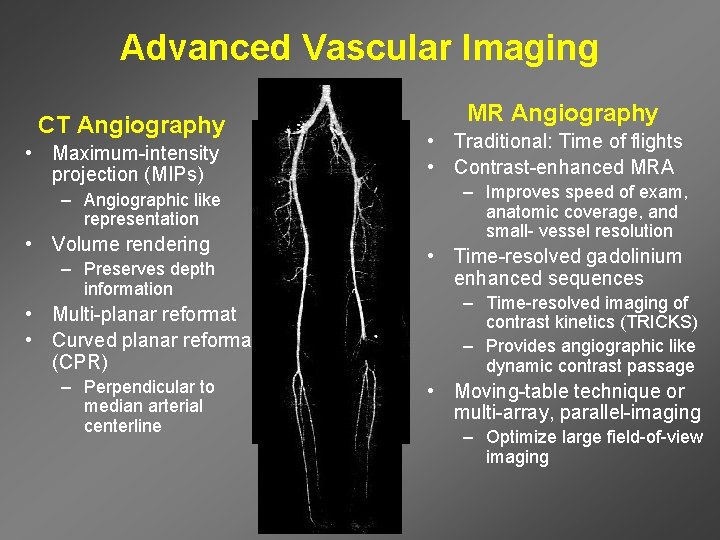

Advanced Vascular Imaging CT Angiography • Maximum-intensity projection (MIPs) – Angiographic like representation • Volume rendering – Preserves depth information • Multi-planar reformat • Curved planar reformat (CPR) – Perpendicular to median arterial centerline MR Angiography • Traditional: Time of flights • Contrast-enhanced MRA – Improves speed of exam, anatomic coverage, and small- vessel resolution • Time-resolved gadolinium enhanced sequences – Time-resolved imaging of contrast kinetics (TRICKS) – Provides angiographic like dynamic contrast passage • Moving-table technique or multi-array, parallel-imaging – Optimize large field-of-view imaging